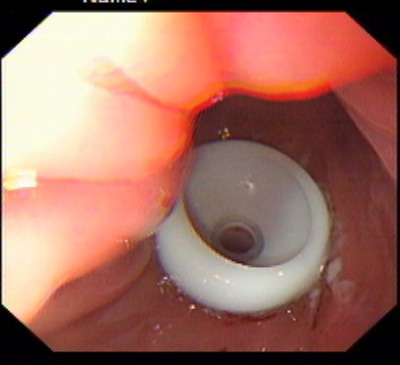

在消化科董蕾主任关心和指导下,消化科王进海教授,张利医师成功地给一位脑出血后吞咽困难的患者实施了经皮内镜下胃造瘘术。

该患者系男性,76岁,脑出血后留有吞咽困难后遗症,不能自主进食,需长期留置胃管供给营养,严重的影响了病人的生活质量和原发病的恢复。经皮内镜下胃造瘘术(Percutaneous endoscpic gastrostomy,PEG)是一种无需常规外科手术和全身麻醉的造瘘技术,可以在胃镜室或病房局麻下进行,因此是一种操作简便、创伤小、安全可靠的方法。该例患者在胃镜室局麻下进行手术,手术过程约10分钟,术后病人无明显不适,3天后即可从造瘘管给食物并出院。

该手术的成功填补了院内空白,丰富了内镜下治疗的内容。对于各种原因造成的长期或较长期不能(一月以上)经口进食者,可通过造瘘管供给病人足够的营养物质,效果优于传统的鼻胃管饲营养,费用又明显低于静脉内营养,是一项值得推广的内镜下较为安全的治疗技术。经皮内镜下胃造瘘术适应证包括:①中枢神经系统或全身性疾病导致的吞咽困难或不能吞咽。如:脑干炎症、变性,脑血管意外,脑肿瘤, 脑外伤;急性呼吸衰竭;系统性硬化症、重症肌无力;完全不能进食的神经性厌食或神经性呕吐导致严重的营养不良,而不能耐受手术造瘘者;②口、咽、喉手术前后及头颈部肿瘤放疗期间,需较长时间营养支持者。③食管广泛瘢痕者;④严重的胆外瘘需将胆汁引回胃肠道者;⑤各种原因所致呼吸功能障碍须气管切开,同时需PEG者;⑥胃肠减压(一月以上的鼻胃管留置者)的目的。